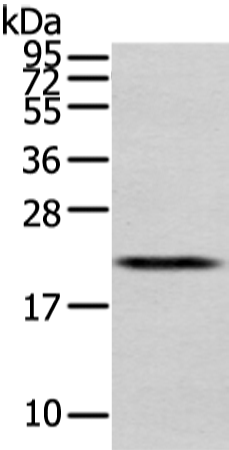

分类: 科研抗体货号: P08902别名: EG1; magicin; 1500003D12Rik应用: WB,IHC反应种属: Human, Mouse, Rat